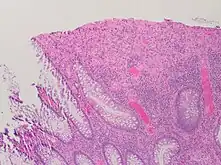

| A micrograph demonstrating cryptitis, a microscopic correlate of colitis. H&E stain. | |

An important investigation in the assessment of colitis is biopsy for histopathology. A very small piece of tissue (usually about 2mm) is removed from the bowel mucosa during endoscopy and examined under the microscope by a histopathologist. A biopsy report generally does not state the diagnosis, but should state any presence of chronic colitis, give an indication of disease activity, as well as state the presence of any epithelial damage (erosions and ulcerations).[6]

Histopathology findings generally associated with chronic colitis include:[6]

Crypt degeneration

Crypt branching and other architectural distortions

Paneth cell (pictured) or gastric metaplasia (only applies in the left colon and rectum)

Other findings include basal plasmacytosis and mucin depletion.[6] Histopathology findings generally associated with active colitis include:[6]

Neutrophilic cryptitis (neutrophils within crypt epithelium)

Crypt abscesses (luminal neutrophilic aggregates)

Gland destruction

Ulceration (seen here as absence of epithelium, and granulation tissue with many fibroblasts)